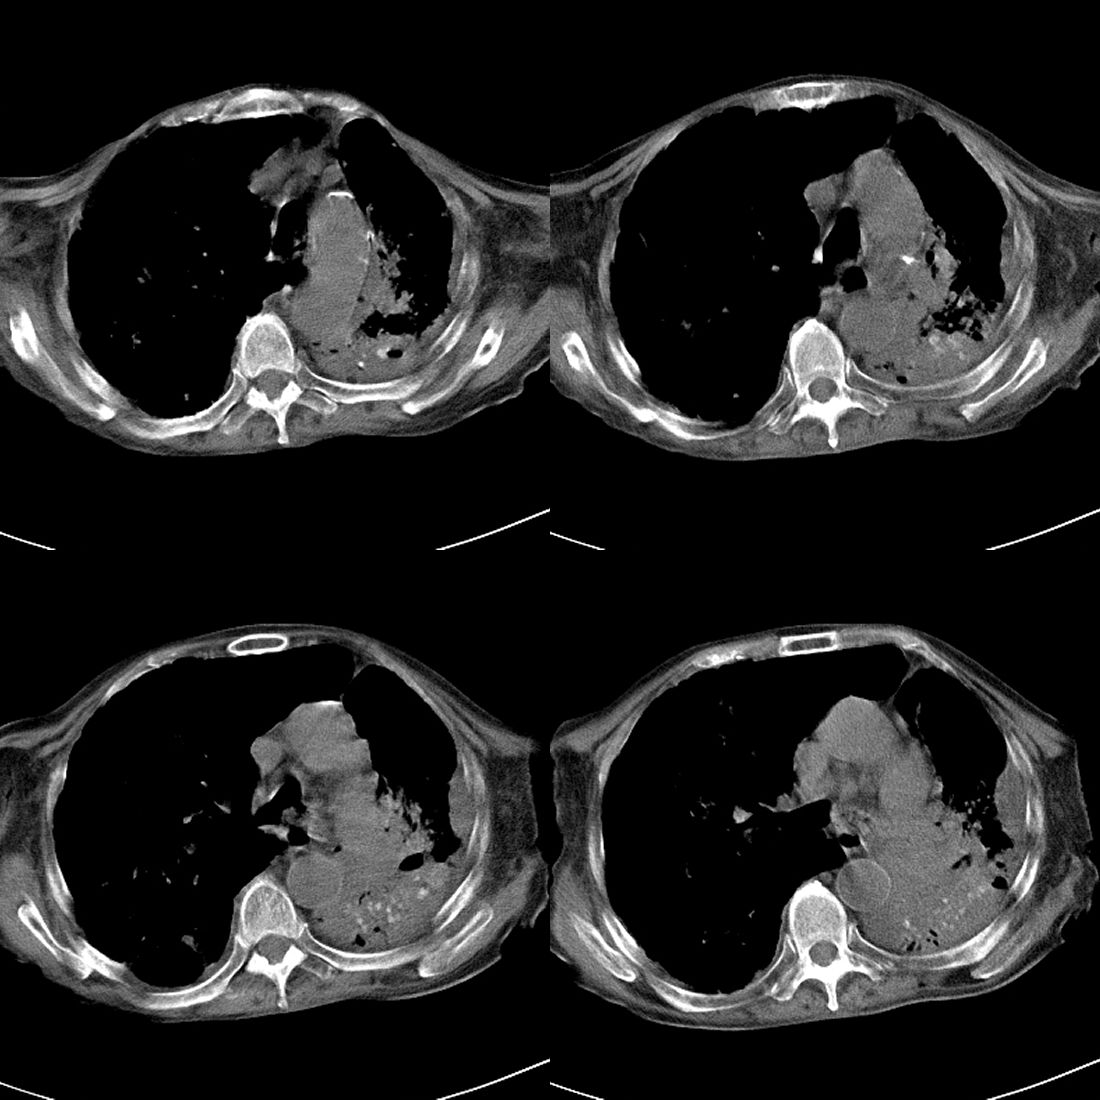

以下是引用liuyue在2008-11-30 6:01:00的发言:[br]双肺继发性肺结核;左侧包裹性积液;建议增强化或支气管镜检查除外左肺占位性病变.

以下是引用吴承学在2008-11-30 8:02:00的发言:[br]双肺继发性肺结核;左侧包裹性积液;建议增强化或支气管镜检查除外左肺占位性病变.[br]